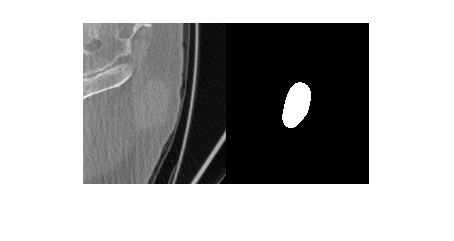

Import a computed tomography (CT) image volume and the corresponding ROI mask volume from the IBSI validation data set [1][2][3] as medicalVolume objects.

unzip("CTImageMaskNIfTI.zip") data = medicalVolume("CT_image.nii.gz"); roi = medicalVolume("CT_mask.nii.gz");

Visualize a slice of the CT image volume and the corresponding ROI.

figure

imshowpair(data.Voxels(:,:,20),roi.Voxels(:,:,20),"montage")